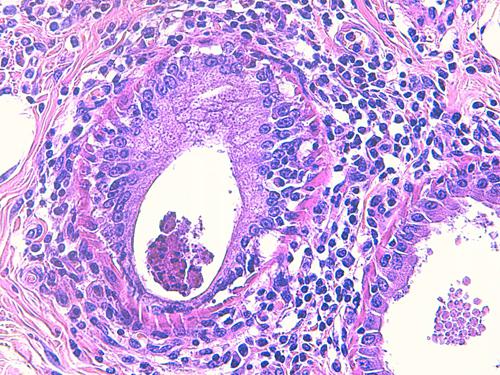

Photo 4 (Hémalun-Eosine X200) peau velue : Vue rapprochée de la Photo 3 montrant

la zone de fissuration de la gaine épithéliale externe d’un infundibula folliculaire avec lyse des

attaches desmosomiales intercellulaires et afflux de granulocytes éosinophiles donnant

naissance à des micro-pustules pariétales multiloculaires.

Légendes de la Photo 4 :

- Double flèche verte : grand axe de l’infundibulum folliculaire

- Double flèche rose : épiderme

- Flèches jaunes : fissuration de la gaine épithéliale externe avec lyse des attaches desmosomiales intercellulaires et afflux de granulocytes éosinophiles

- Ronds marrons : parakératose

- Étoiles rouges : micro-pustules pariétales multiloculaires (folliculite murale) et luminales obstruant l’abouchement folliculaire

- Étoiles turquoises : à gauche infiltrat inflammatoire dermique (au milieu en bas, erreur)

- Étoile vertes : orthokératose